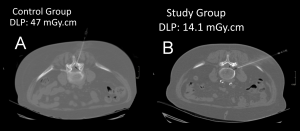

The Dose Length Product (DLP) in the study group was significantly lower than in the control group (Table 2; Figure 1).

The study group had a mean total DLP of 134.71 mGy.cm, compared to 313.13 mGy.cm in the control group. This equates to a dosage reduction of 56.97%.

The mean DLP for minimal dose acquisitions was 9.77 mGy.cm in the study group against 44.71 mGy.cm in the control group. This equates to a dosage reduction of 78.4%.

The needle tip visibility did not differ significantly between the two groups (p = 1.0, Chi-square test) (Figures 2, 3, 4, and 5). The needle tip was visible in nearly every patient in this study (170 out of 171).